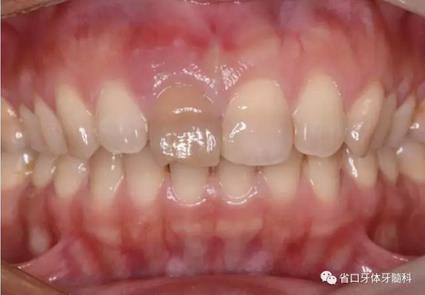

1.?病例簡介 43歲女性患者,主拆:右上前牙松動(dòng)不適數(shù)日要求修復(fù)?,F(xiàn)病史:患者數(shù)年前右上前牙因“齲壞”于外院行根管治療(具體不詳),數(shù)日前牙冠松動(dòng)不適,現(xiàn)覺影響咀嚼及美觀,遂來我院要求進(jìn)一步診治。否認(rèn)高血壓、心臟病等重大疾病,否認(rèn)結(jié)核、肝炎等傳染病史,否認(rèn)手 術(shù)、輸血史等,未發(fā)現(xiàn)藥物過敏。無吸煙習(xí)慣。臨床檢查:口外觀顏面基 本對稱,皮膚無紅腫破潰,顳下頜關(guān)節(jié)區(qū)無彈響、雜音、壓痛,開口度約 37mm,開口型“↓”,頜下、刻下和頸部未及腫大淋巴結(jié)。中位笑線??趦?nèi)檢查,口腔衛(wèi)生可,色素(+),BOP(-),PD=2mm,上頜右側(cè)中切 牙冠部變色,冠根折斷至齦下3mm,叩不適,松動(dòng)Ⅱ°~Ⅲ°。牙齦稍紅, 齦緣水平及齦乳頭高度可,屬于中厚齦生物型,附著齦寬度約5mm,唇系帶附著可。上頜右側(cè)中切牙缺牙間隙與對側(cè)同名牙一致,約>7mm,修復(fù)空 間良好。與對頜牙覆合覆蓋正常。MCT檢查示上頜右側(cè)中切牙冠根折斷至骨 下,根管內(nèi)見充填物,根充不全,根尖見陰影,大小約3mm×3mm。牙槽窩根方可用骨量可,唇側(cè)骨壁完整,冠方骨壁厚度約1mm。

圖1 術(shù)前口內(nèi)照

圖2 術(shù)前口內(nèi)照

圖3 術(shù)前口內(nèi)照